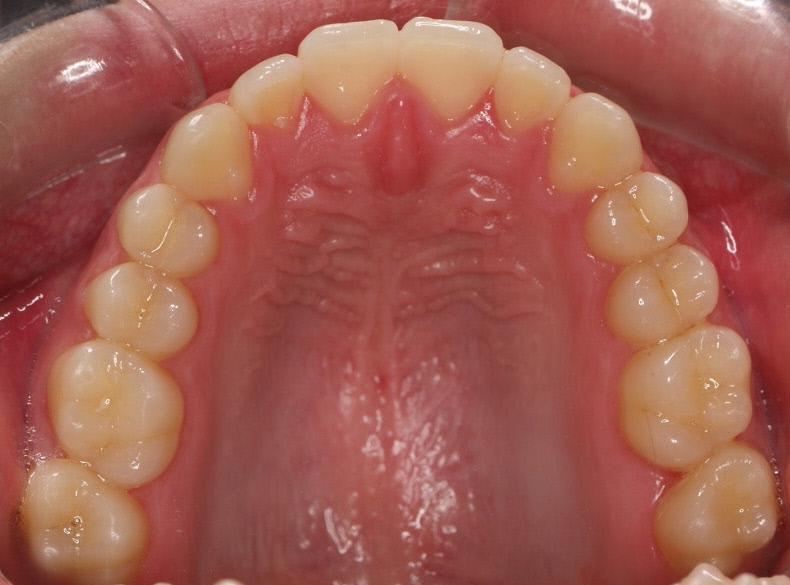

Chica de 17 años tratada en 1 año con stripping en los dientes inferiores